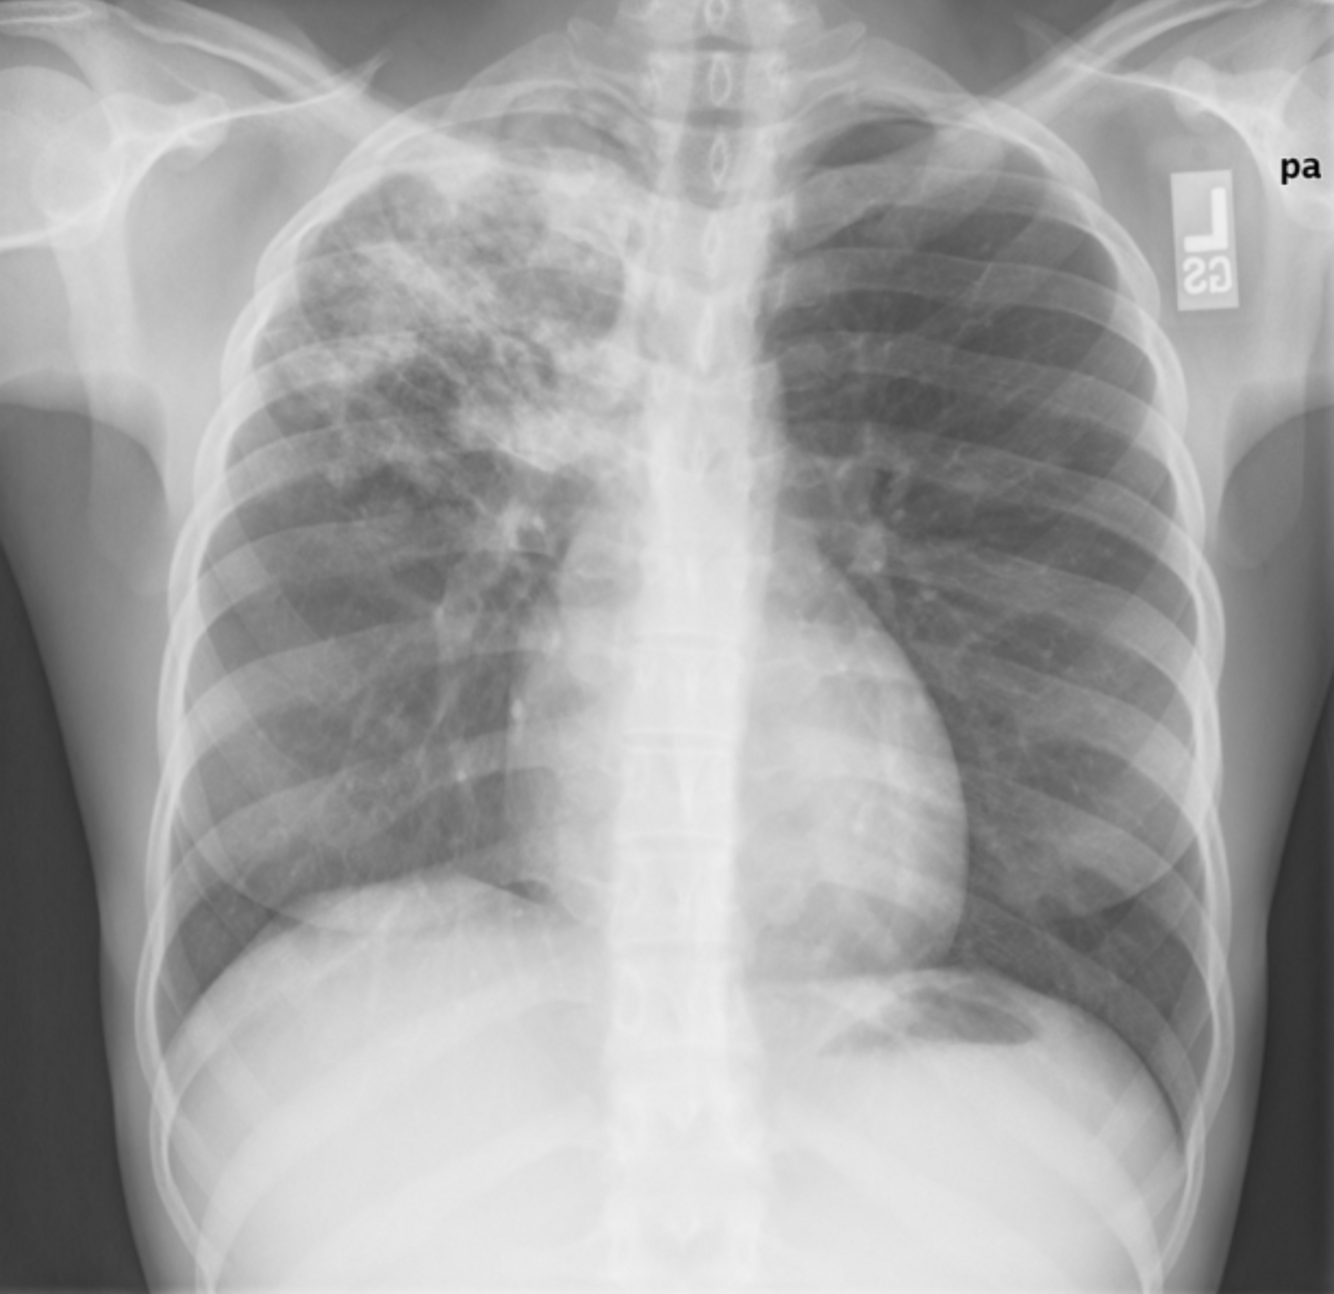

20 F, originally from the Philippines, presents with 4 weeks of cough, fever, night sweats, and 5 kg weight loss.

He reports mild hemoptysis.

T 38.3°C, HR 95, RR 20, BP 110/70, SpO₂ 95% RA.

Exam: mild crackles over the right upper lung.

CXR >

Most likely diagnosis?

How is diagnosis confimed?

A

Pulmonary TB ~Mycobacterium tuberculosis.

Gold standard for diagnosis:

- Sputum AFB smear & culture 3 x early-morning samples

Others:

1. NAAT / PCR

- Rapid detection + rifampin resistance

1. TB skin test (TST) or IGRA Detects latent infection

2. HIV testing

- Co-infection risk high